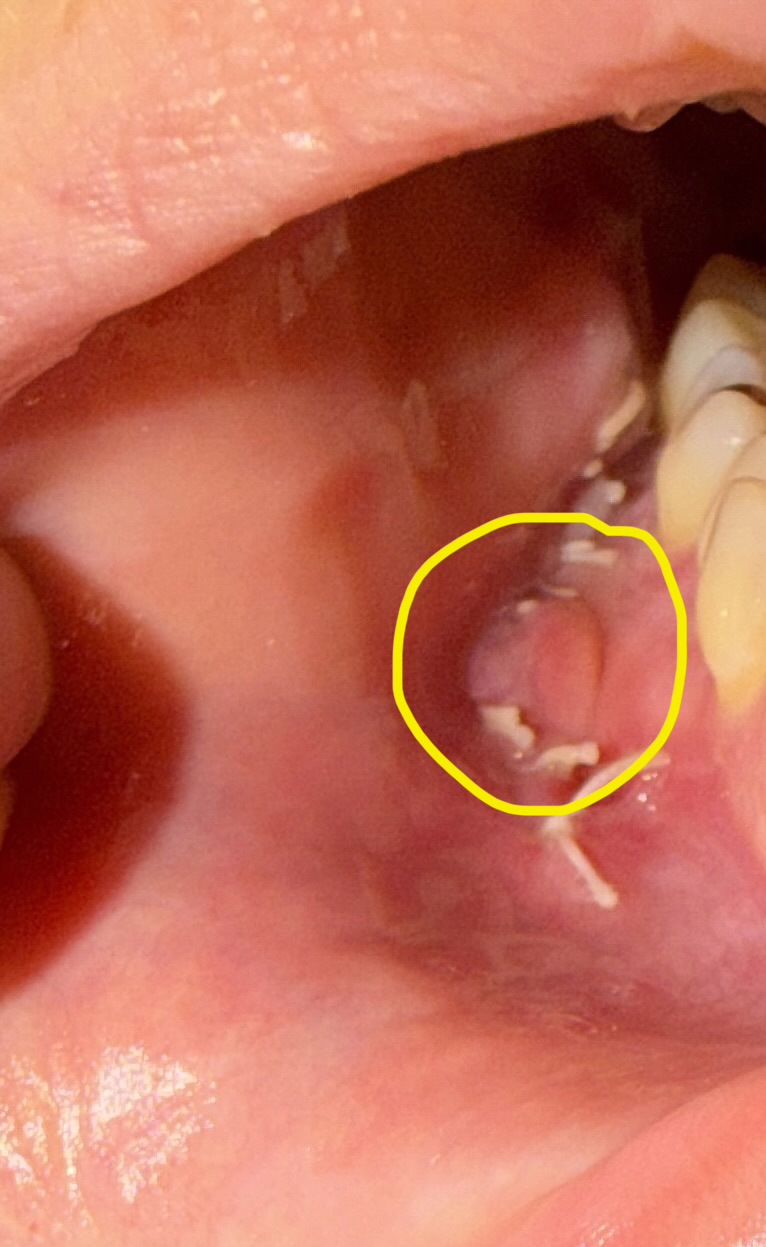

이거 잇몸염증일까... ㅠㅠㅠㅠㅠㅠ

다른쪽입은 안이런데 한쪽이 이래 ㅠㅠㅠ

그래서 그부분 심부볼이 엄청 딱딱함 (다른쪽은 안그랴 ㅠㅠ)

안에 몽우리? 처럼 이렇게되있는데.. 이거 뭐 수술해야하고 그런거아니겟지.. ㅋ

윤곽2종한지 5일째...